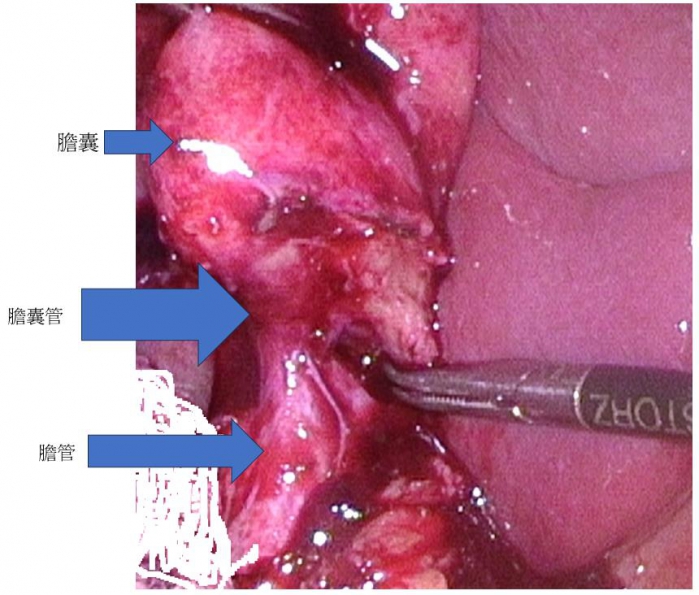

【記者林獻元台中報導】衛生福利部豐原醫院日前收治一名謝姓男士64歲,因腹痛又加上臉色發黃的狀況到醫院就診,外科主任袁天民醫師初步診視後為急性膽囊炎。術前安排核磁共振檢查發現為Mirizzi症候群(為膽結石卡在膽囊管或膽囊頸部)症候群,緊急安排手術,住院5日後已康復出院。

袁天民表示,Mirizzi症候群主要發生在膽管與膽囊的接口處,因膽囊頸部的結石壓迫膽管,造成整個膽管跟膽囊管的結構無法清楚被看見,若採用傳統腹腔鏡膽囊切除手術,可能在手術中造成對膽管的損傷。